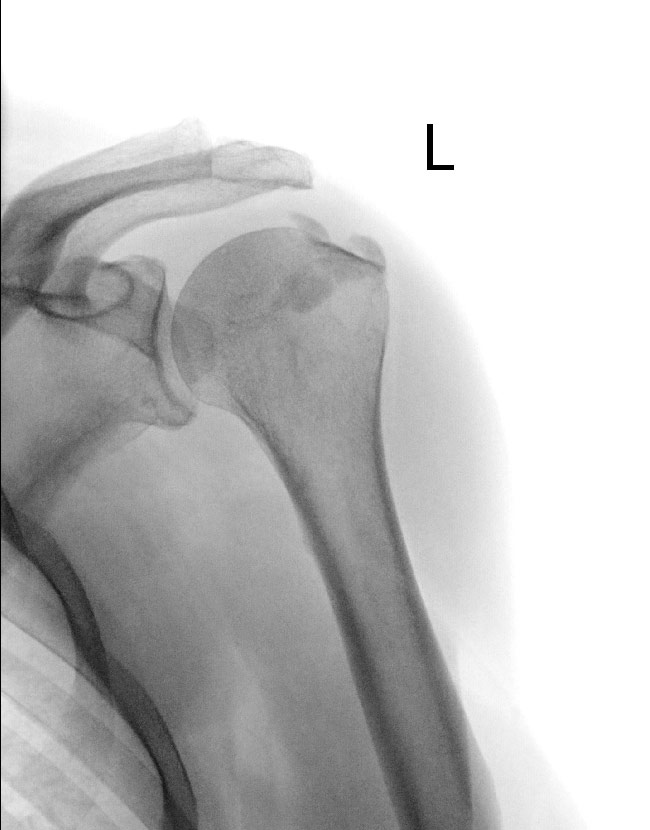

Bei der Kalkschulter handelt es sich in der Regel um Verkalkungen bzw. Der Tendinosis calcarea auch kalzifizierende Tendinitis oder Sehnenverkalkung liegen kalkartige Ablagerungen Kalziumsalze im Ansatzbereich von Sehnen zugrunde. Schmerzen Bewegungseinschränkungen nächtlicher Ruheschmerz Begleiterkrankungen.

Bei der Kalkschulter handelt es sich in der Regel um Verkalkungen bzw. Du kannst durch die richtige Bewegung gezielt gegensteuern. Ich leide seit 2 Wochen an einer akuten Entzündung tendinitis calcarea der li Schulter und nehme 2x tgl Diclofenac 50 mg. Die Tendinitis Calcarea oder auch Kalkschulter ist eine Erkrankung die insbesondere Frauen zwischen dem 30. Sie wird meisten erst relativ spät bemerkt da sie zwischen den sogenannten Schüben relativ schmerzfrei verläuft. Tendinitis Sehnenreizungen Eine Tendinitis im Schulterbereich ist oft Folge einer mechanischen überstrapazierung. Unter einer Tendinosis calcarea versteht man die Einlagerung von Kalkherden in eine Sehne die zu Schmerzen führt. Symptome und Verlauf der Tendinitis. Auf sportliche Aktivitäten oder gymnastische Übungen sollte besser verzichtet werden weil sie.